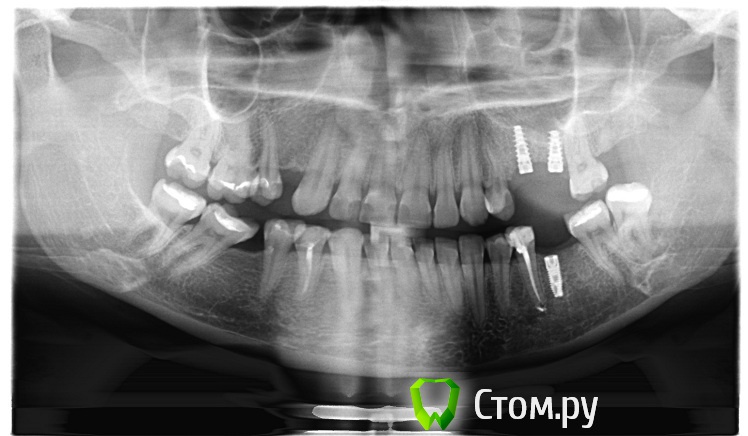

Очень нужен совет профессионала.. у меня проблема   стирание нижних зубов, крошение передних. сходила не к одному ортодонту, и каждый предлагает свое лечение, одни, что нужны брекеты, другие что не нужны..В интернете я вычитала что при уже установленных имплантов брекеты не ставят. (сама коронковая часть зуба не стоит, только пока в десне сам имплант).Другие говорят что после того как установятся жевательные зубы, и нормализуется жевательная функция и тогда передние зубы перестанут крошиться и стирать нижние. Можно сделать реставрацию и виниры. Мнения расходятся. Мой челюстно-лицевой хирург против всех этих брекетов и говорит что после установки жевательных зубов ситуация измениться и все станет на свои места кусательные будут кусать жевательные будут жевать.Если честно уже вообще боюсь обращаться к какому либо врачу  в Ростове я так понимаю специалистов вообще нет. Боюсь что если мне поставять брекеты то проблем не оберусь вообще.. вдруг появятся боли , щелчки. сейчас проблем не наблюдаю.. не жалуюсь.  Единственное что вижу что лечить у нас не умеют  .. поставили пломбы почему то отказали во вкладках (зубы живые)  при смыкании нет контактов между верхом и низом.. КАК ТАК МОЖНО ЛЕЧИТ??? Прост крик души.  3 года подряд не вылазию от стоматологов.. муж говорит уже проще вырвать и поставить челюсти... ПОМОГИТЕ СОВЕТОМ!!!

post-38409-0-42250700-1410279954_thumb.pngpost-38409-0-30034200-1410279968_thumb.pngpost-38409-0-53504700-1410279995_thumb.pngpost-38409-0-83922200-1410280650_thumb.jpgpost-38409-0-90569300-1410281193_thumb.jpgpost-38409-0-02837100-1410282869_thumb.jpgpost-38409-0-46746600-1410283445_thumb.jpg

Поддерживаю.Показания к ортодонтическому лечению  есть.Подготовка к рациональному протезированию одна из  целей ортодонтического лечения данного случая.